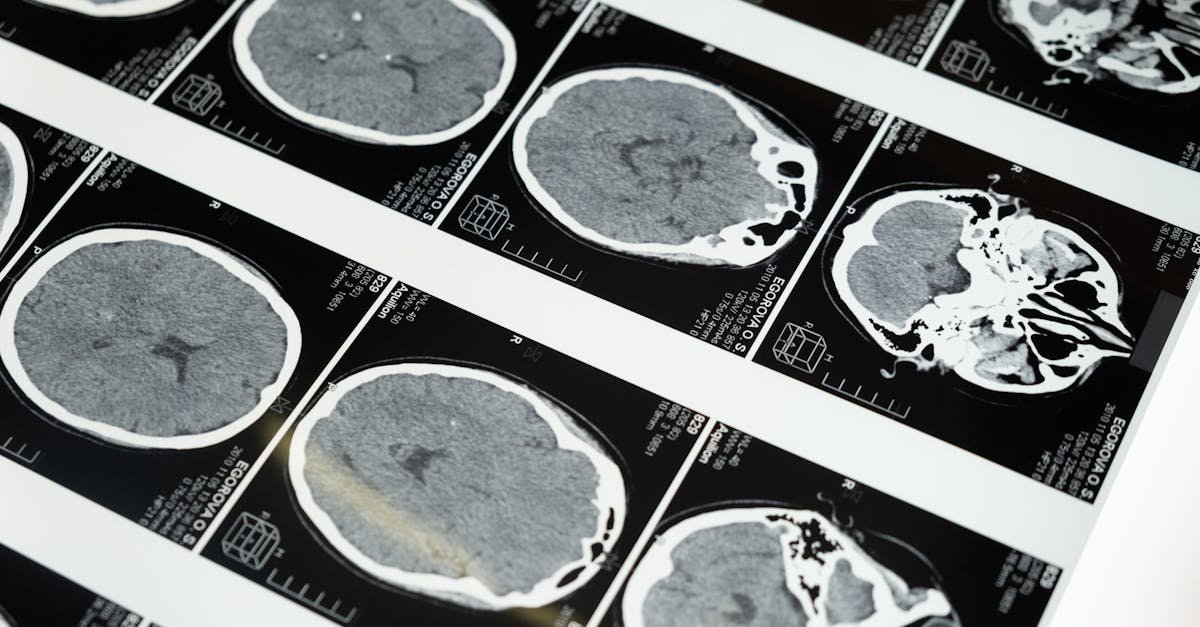

Stroke represents a significant health crisis, often resulting in severe physical and cognitive impairment. It occurs when blood flow to the brain is interrupted, leading to potential cell death. The severity of a stroke largely depends on its type—ischemic or hemorrhagic—and the area of the brain affected. Prompt medical intervention can mitigate long-term consequences, but many survivors face challenges that alter their daily lives.

Strokes can be categorized primarily into two types: ischemic and hemorrhagic. Ischemic strokes occur when a blood clot obstructs blood flow to the brain. This type is the most common, accounting for approximately 87% of all stroke cases. Hemorrhagic strokes, on the other hand, arise from a rupture of blood vessels, leading to bleeding in or around the brain. The prognosis for each type varies significantly, with ischemic strokes often linked to conditions like heart disease and diabetes, while hemorrhagic strokes may be associated with high blood pressure and aneurysms.

The consequences of a stroke can be profound and wide-ranging. Survivors may experience various disabilities depending on the area of the brain affected. Common repercussions include difficulties with speech, movement, and cognitive functions. Emotional and psychological impacts also play a critical role in recovery, as many individuals may confront depression and anxiety. Rehabilitation processes can be lengthy and require a multi-disciplinary approach to address the complex aftermath of stroke effectively.